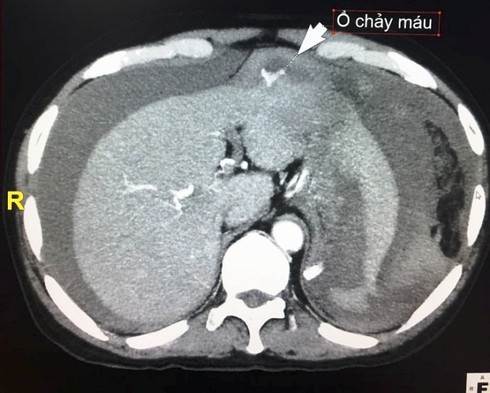

Bệnh nhân Đinh Minh T. bị ngã, khiến u gan bị vỡ. |

Chiều 14/3, Bệnh viện Hữu nghị Việt Nam – Cu Ba Đồng Hới vừa tiến hành cấp cứu thành công cho anh Đinh Minh T. (trú tại huyện Minh Hóa, tỉnh Quảng Bình) nhập viện do bị vỡ u gan, máu tràn đầu ổ bụng.

Trước đó, vào ngày 13/3, anh T. được đưa vào Bệnh viện Hữu nghị Việt Nam - Cu Ba Đồng Hới cấp cứu trong tình trạng sốc mất máu. Tại đây, bệnh nhân được các nhân viên y tế vừa tiến hành hồi sức tích cực vừa tiến hành xét nghiệm, chụp phim...

Qua thăm khám, các bác sĩ phát hiện anh T. bị vỡ u gan hạ phân thùy III và có hơn 2 lít máu trong ổ bụng. Các bác sĩ vừa tiến hành truyền máu và các chế phẩm thay thế máu vừa điều trị bằng phương pháp nút mạch. Sau đó, tiến hành chọc dẫn lưu ổ bụng rút ra 2 lít máu.